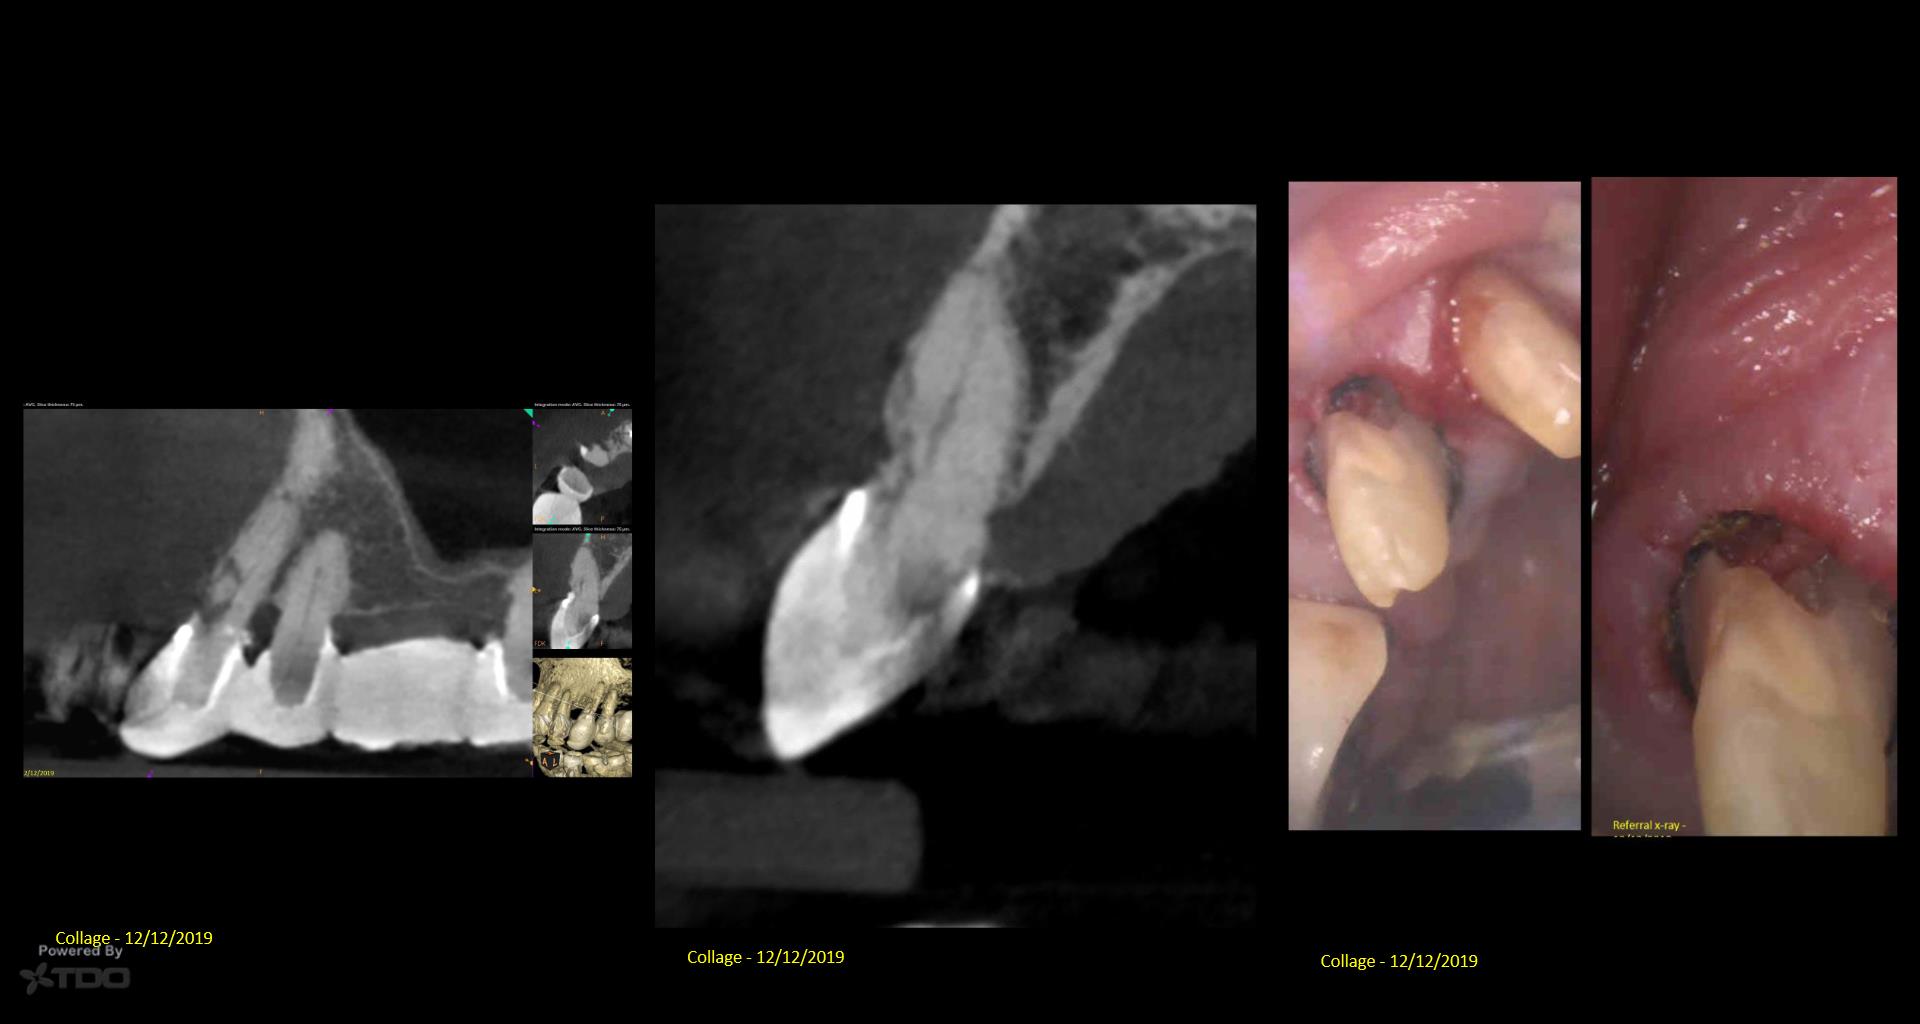

I posted this last month after the consult. There was mixed TDO advice—some said “do it” and others said monitor. Reluctantly, I did it Monday. I couldn’t really address the ECIR that was sub-osseous without removing way too much bone. I just hit it with the Pear Diamond as well as I could. Time will tell if it was a fool’s errand. I video’d the whole thing but don’t have the time to edit it. gbc